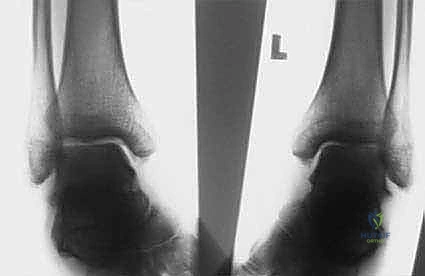

الأشعة السينية العادية (X-rays) أثناء الوقوف (Weight-bearing) هي الأساس. يقوم الدكتور هطيف بقياس زوايا محددة بدقة هندسية:

* زاوية ميري (Meary's Angle): لتقييم مدى تقوس منتصف القدم.

* زاوية ميل الكعب (Calcaneal Pitch Angle): تكون زائدة بشكل كبير في القدم الجوفاء.

* زاوية هيبس (Hibbs Angle): لتقييم التشوه في مقدمة القدم.

في الحالات المعقدة، أو إذا كان هناك اشتباه في تآكل غضروفي أو التحام عظمي غير طبيعي (Tarsal Coalition)، يتم طلب الأشعة المقطعية (CT Scan) للحصول على رؤية ثلاثية الأبعاد للعظام. قد يُطلب الرنين المغناطيسي (MRI) لتقييم حالة الأوتار والأربطة.